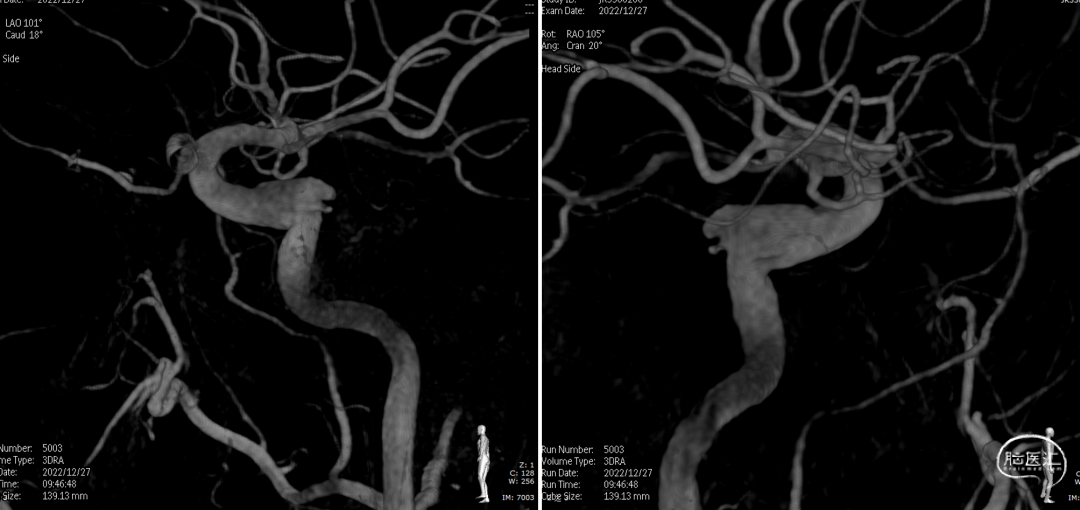

术后复查右颈内动脉3D重建

术后3D重建

术后3D图像及透视

术前、术后3D图像对比